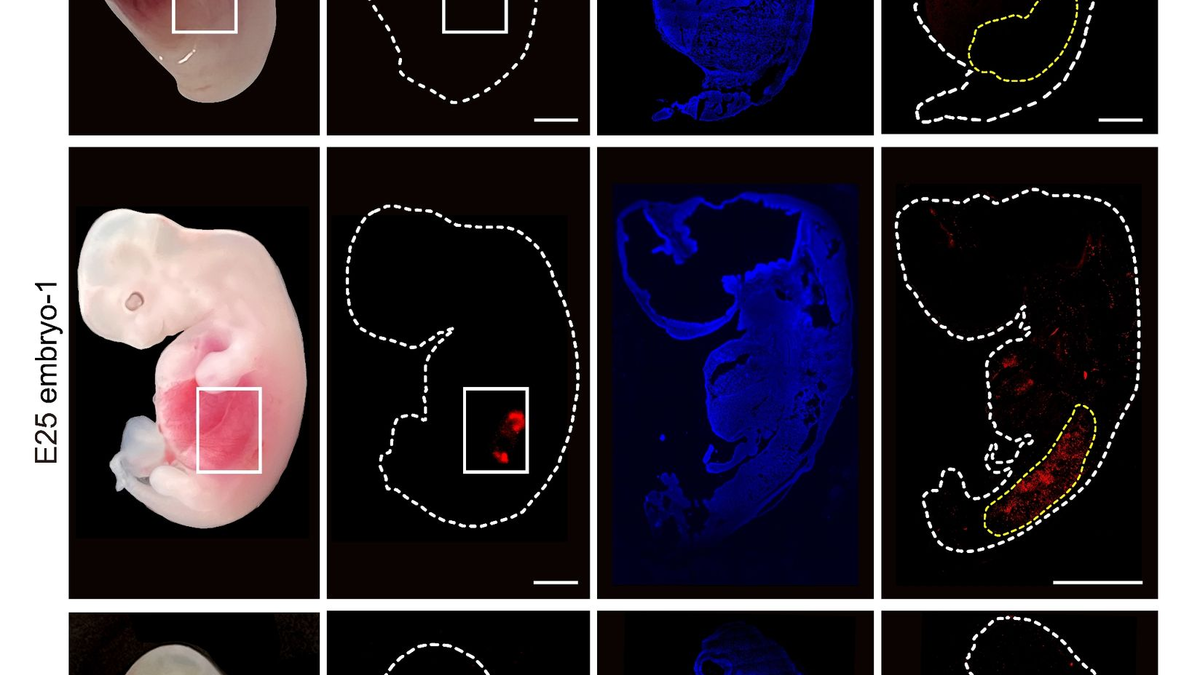

Die Schweineembryos pflanzten die Wissenschaftler in Säue ein, wo sie sich bis zum 25. oder 28. Tag entwickeln konnten. Es gab einige Embryonen, bei denen sich eine Niere aus überwiegend menschlichen Zellen im Vergleich zu nicht behandelten Schweineembryonen normal entwickelt hatte. Das Verfahren ist aber noch verbesserungsbedürftig: «Der Gesamtanteil degenerierender Schweinembryonen ist hoch, und es muss beurteilt werden, ob dies teilweise mit dem Chimärismus oder anderen Aspekten des Injektionsverfahrens zusammenhängt», schreiben die Studienautoren.